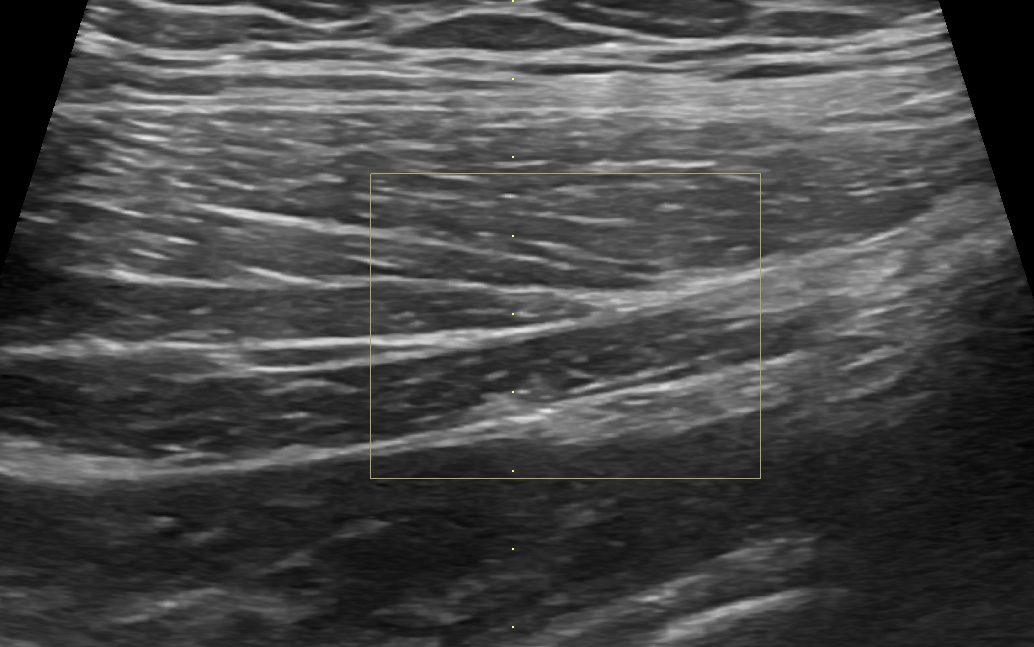

透過超音波檢查,我們可以區分出這幾條肌肉的相對位置,甚至跟對側比較,去看是否肌肉源頭(origin)、連接在骨頭處(insertion)或是肌鍵與肌肉中間的部分有撕裂或部分斷裂的狀況。

(跟對側比較,臀中肌的後側纖維比較不平整、比較腫脹且血流增加,暗示這邊有一個撕裂處)